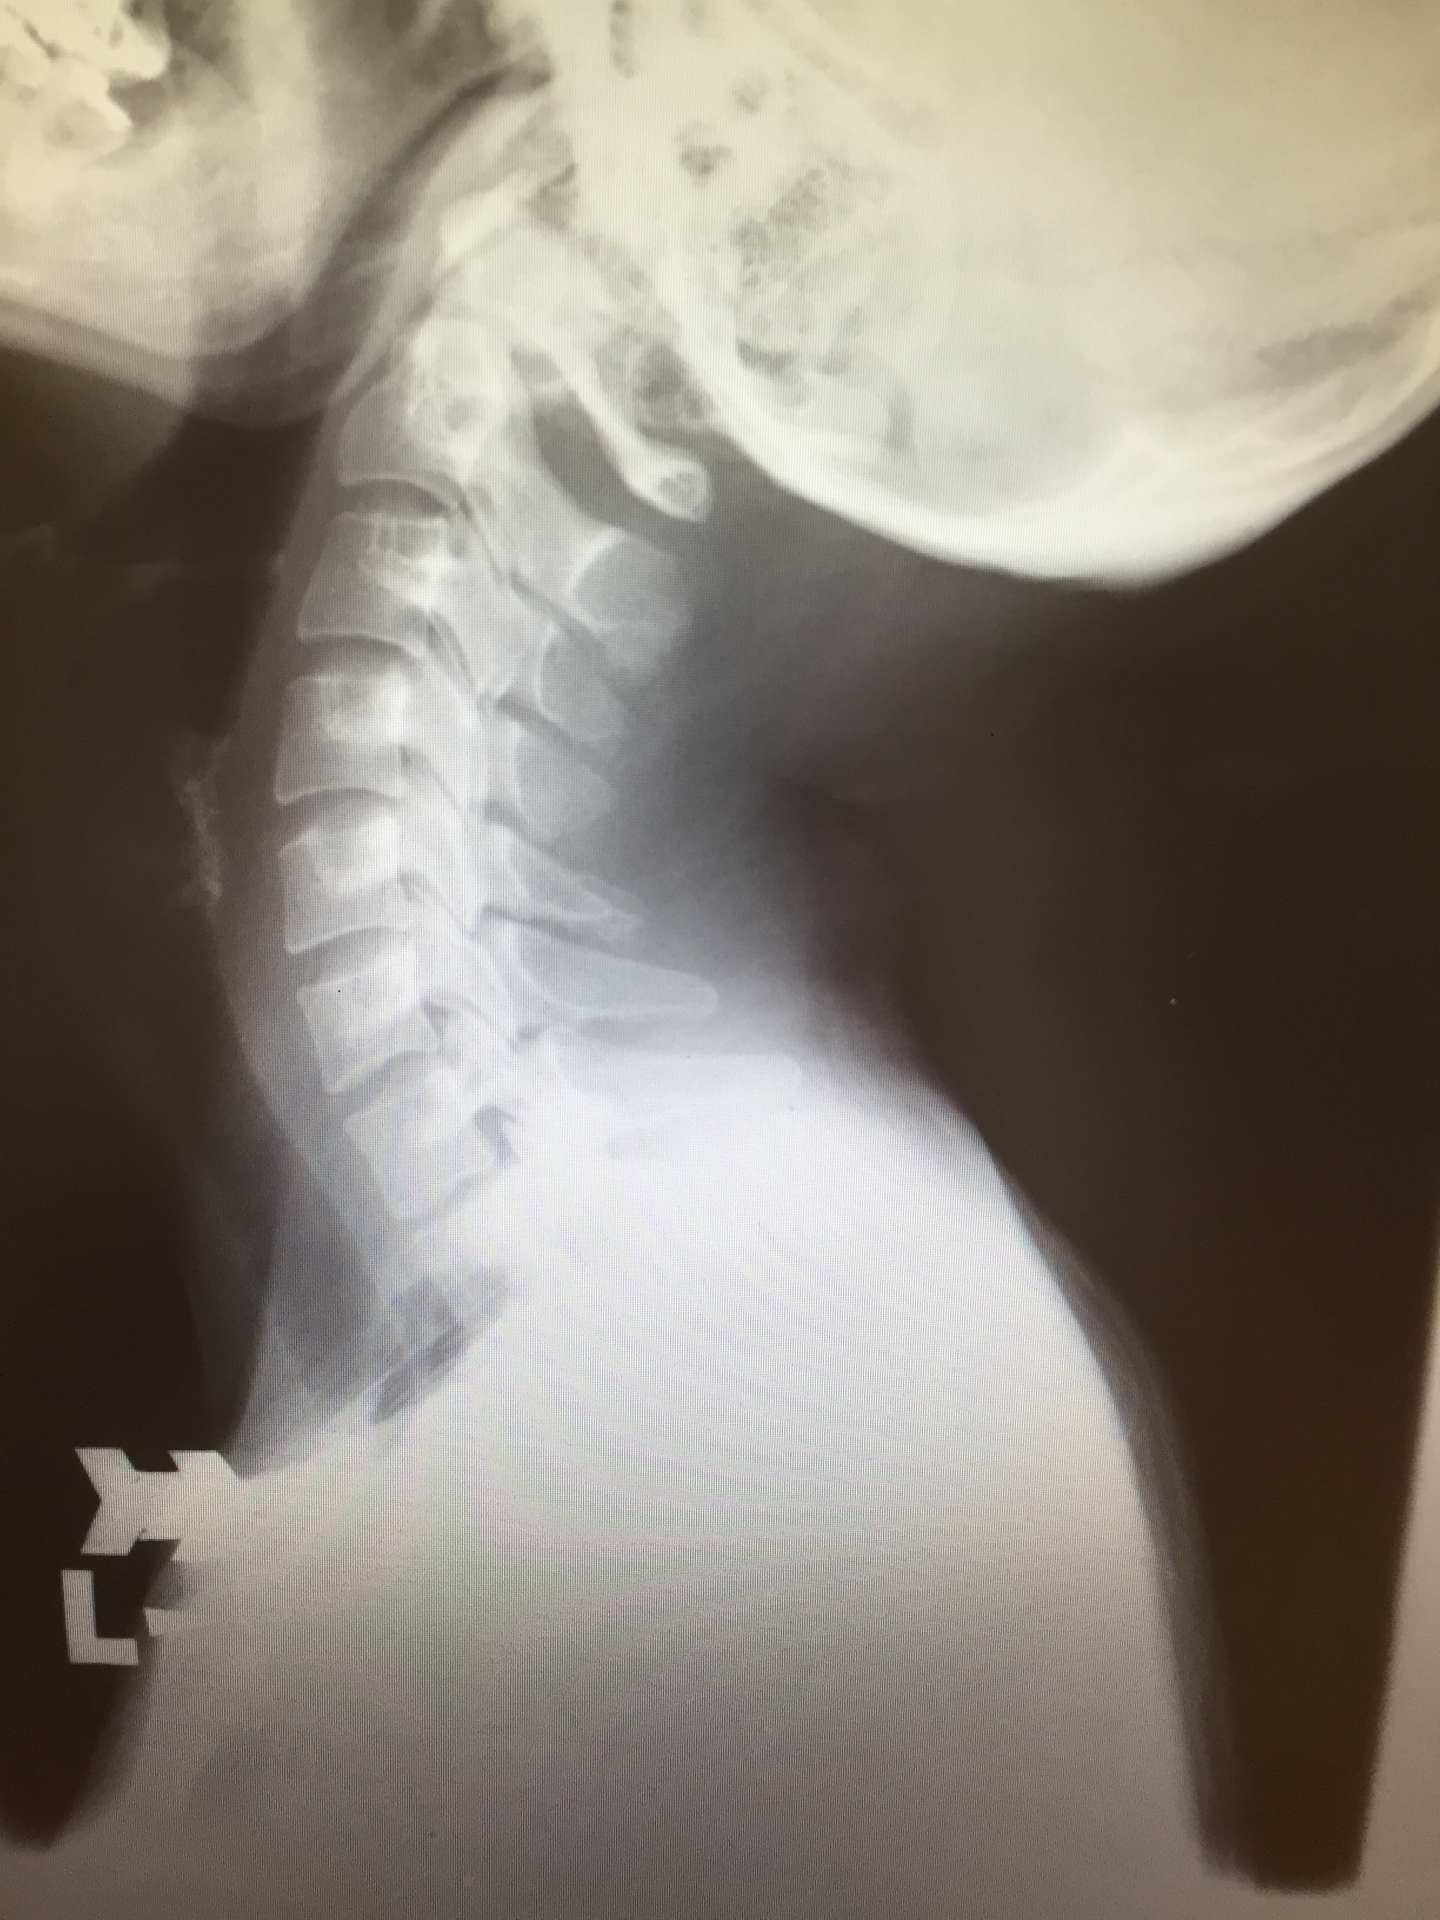

頚部のレントゲン

専門医による検査と診断

交通事故の後は、見た目に異常がなくても、体の深部に影響が及んでいる場合があります。当院では、整形外科専門医が医学的根拠に基づき診察を行い、安心して治療を受けていただける体制を整えています。

レントゲンやエコー検査を用いて、骨・関節・筋肉の状態を詳しく調べます。症状が軽い場合でも、まずは骨折や神経障害といった重い異常がないか確認することが大切です。必要に応じ、精密検査が可能な施設と連携をとり詳細を調べていきます。

原因を早期に追求することが今後の治療戦略に大きな影響を与えますので、気になる症状がある方は一度ご相談ください。